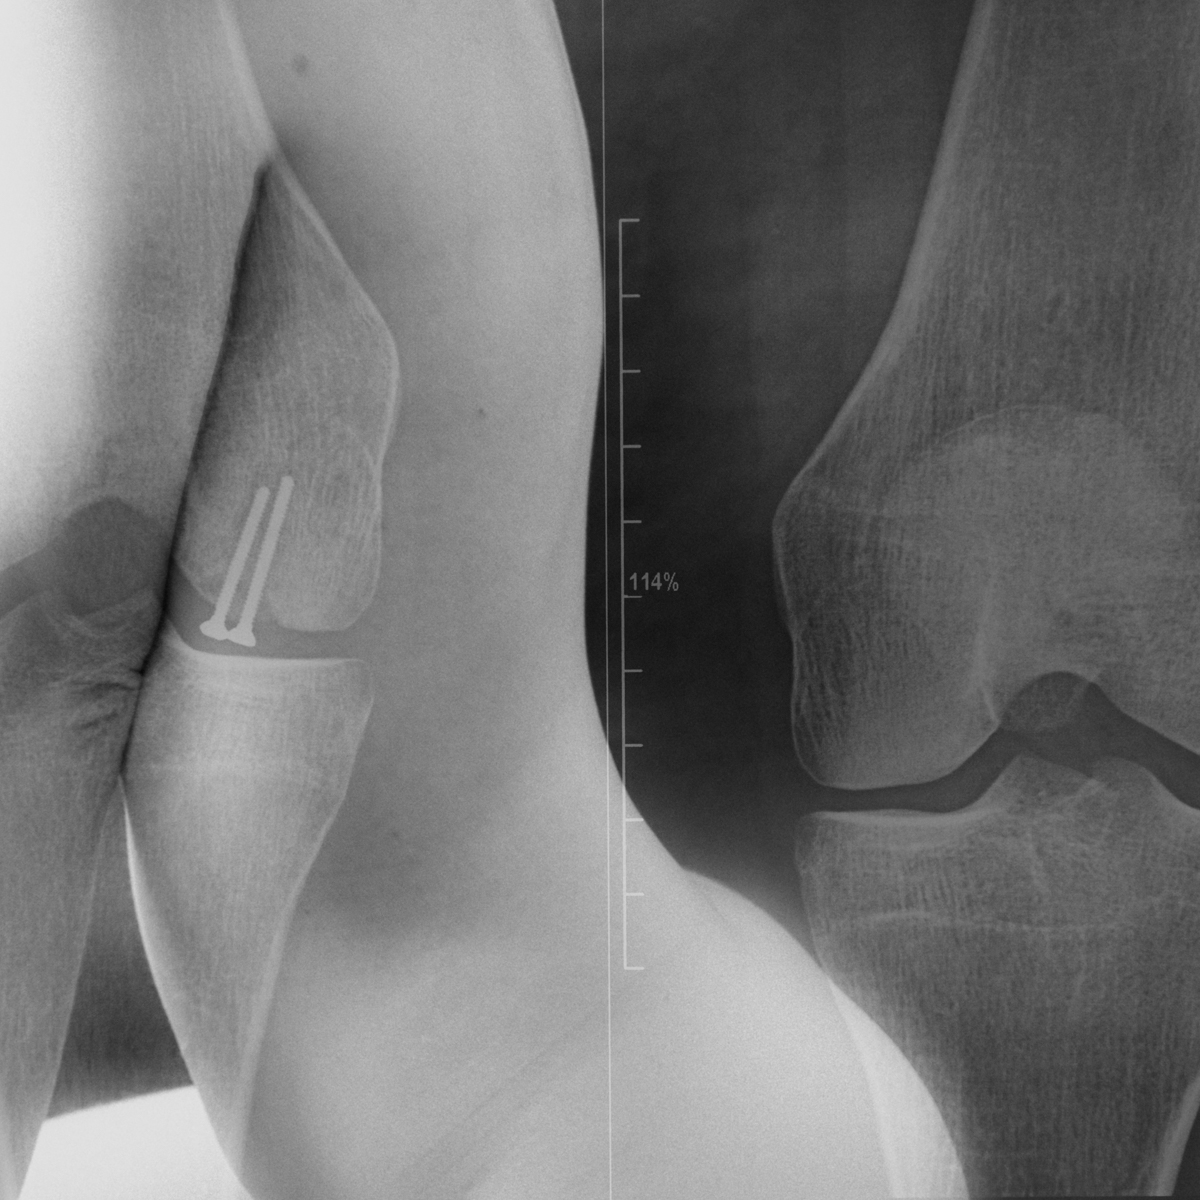

SURFACES SENSIBLES — À la frontière de l'autoportrait, "Surfaces sensibles" retranscrit une partie de ma réalité et brouille les limites entre l'intime anatomique et l'émotionnel.

La science produit les images les plus concrètes et les plus neutres pour illustrer les affects. Pourtant, par leur froideur et leur distance, elles sont les moins aptes à témoigner des émotions. Chaque radiographie, scanner, IRM correspond à une douleur ou à un mal-être spécifique.

Depuis peu, ces images ne sont plus seulement des réminiscences de douleurs passées, mais également des matériaux bruts inspirants pour ma pratique photographique. À partir des radios originelles, j'ai utilisé plusieurs techniques telles que la superposition et le tirage argentique dans le but de me rapprocher d'une perception alternative de ce corps irradié.